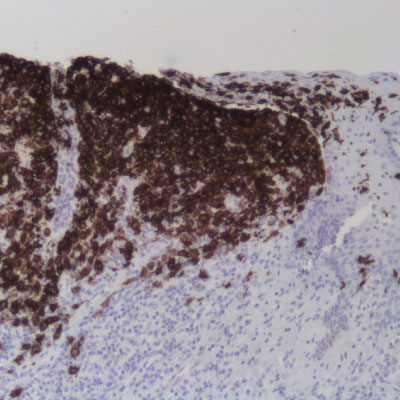

Inmunohistoquímica (IHC)

La inmunohistoquímica (IHC) es una técnica utilizada en el campo de la anatomía patológica y la investigación biomédica para visualizar la presencia, distribución y localización de proteínas específicas en muestras de tejido utilizando anticuerpos específicos y técnicas de tinción. La técnica de IHC es fundamental en la identificación de proteínas específicas en el tejido y es ampliamente utilizada en el diagnóstico de enfermedades, la caracterización de tumores, la investigación biomédica y la identificación de biomarcadores.